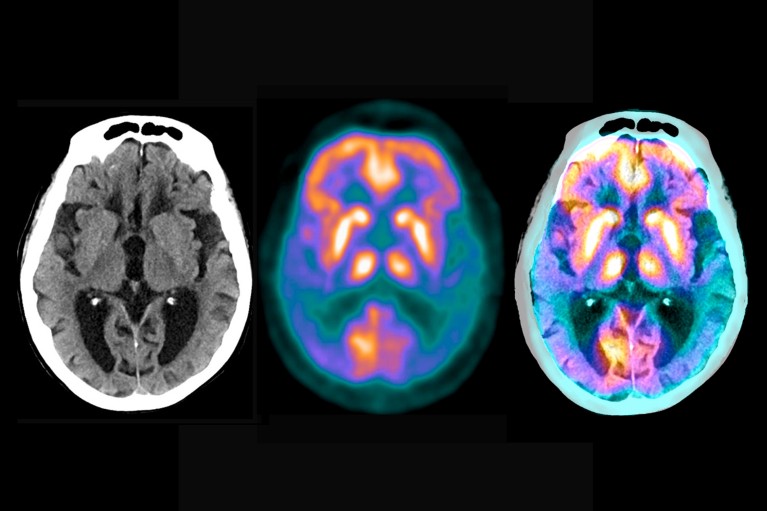

脑部扫描揭示了阿尔茨海默病造成的损害程度

试验的关键是一系列敏感的新生物标志物——大脑或血液的测量,可以读出疾病状态。脑部扫描监测淀粉样斑块和 tau 蛋白缠结的存在和严重程度;血液或脑脊液测试可测量病理链中的许多其他分子,例如不同形式的淀粉样蛋白和 tau 蛋白。研究人员期望他们产生的大量分子和临床数据将有助于揭示更多关于阿尔茨海默氏症的机制。 “目前的证据表明 tau 是阿尔茨海默病症状、残疾和最终死亡的始作俑者,”Boxer 说。 “但这个假设需要在人类身上进行测试。”

阿尔茨海默病的典型特征:斑块(大块)和 tau 蛋白缠结(小块)